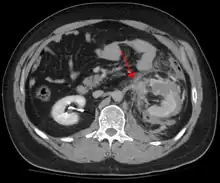

Le traumatisme abdominal contondant (TAC) représente 75 % de tous les traumatismes contondants et constitue l'exemple le plus courant de cette blessure[4]. 75 % des TAC surviennent lors des accidents de la route[5], dans lesquels une décélération rapide peut propulser le conducteur contre le volant, le tableau de bord ou la ceinture de sécurité[6], provoquant des contusions dans les cas moins graves, ou la rupture d'organes internes en raison d'une brève augmentation de la pression intraluminale dans les cas les plus graves, en fonction de la force appliquée. Au début, il peut y avoir peu d'indications que des lésions abdominales internes graves se sont produites, ce qui rend l'évaluation plus difficile et exige un haut degré de suspicion clinique[7].

Deux mécanismes physiques de base entrent en jeu dans le risque de lésion des organes intra-abdominaux : la compression et la décélération[8]. Le premier résulte d'un coup direct, tel qu'un coup de poing, ou d'une compression contre un objet non flexible tel qu'une ceinture de sécurité ou une colonne de direction. Cette force peut déformer un organe creux, augmenter sa pression intraluminale ou interne et éventuellement conduire à sa rupture.

La décélération, en revanche, provoque un étirement et un cisaillement aux points d'ancrage du contenu mobile de l'abdomen, comme l'intestin. Cela peut provoquer une déchirure du mésentère de l'intestin et des lésions des vaisseaux sanguins qui parcourent le mésentère. Des exemples classiques de ces mécanismes sont une déchirure hépatique le long du ligament rond et des lésions des artères rénales.